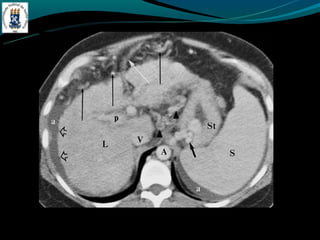

-TC: Esplenomegalia, formação de colaterais, ascite, e pode ter

alta atenuação na fase arterial.

TROMBOSE DA VEIAPORTA -Complicação de cirrose -Invasão ou compressão tumoral -Hipercoagulabilidade -Inflamação -Incidência de 5% na hipertensão portal e próximo de 30% no CHC -TC: Esplenomegalia, formação de colaterais, ascite, e pode ter alta atenuação na fase arterial. -RM: trombo agudo hiper em T1 e T2, crônico hipo em T1 e hiper em T2.